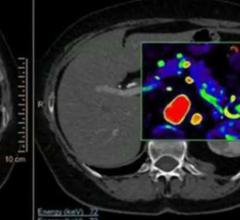

The last 12 months have seen significant growth in the positron emission tomography/computed tomography (PET/CT) segment of radiology, from both a manufacturing and a research perspective. One brand-new system received U.S. Food and Drug Administration (FDA) market clearance just months ago, while another started making its way into hospitals in the second half of last year. Several manufacturers also released software updates to help integrate PET/CT imaging into radiation therapy planning and execution. The increased interest was supported by several large studies exploring the advanced applications of PET/CT in oncology imaging.

In the world of molecular imaging, PET/MR is a wild card. But it’s a wild card that’s ready to be played. Three major vendors offer commercial products. The images are spectacular. So…what’s the hold up?